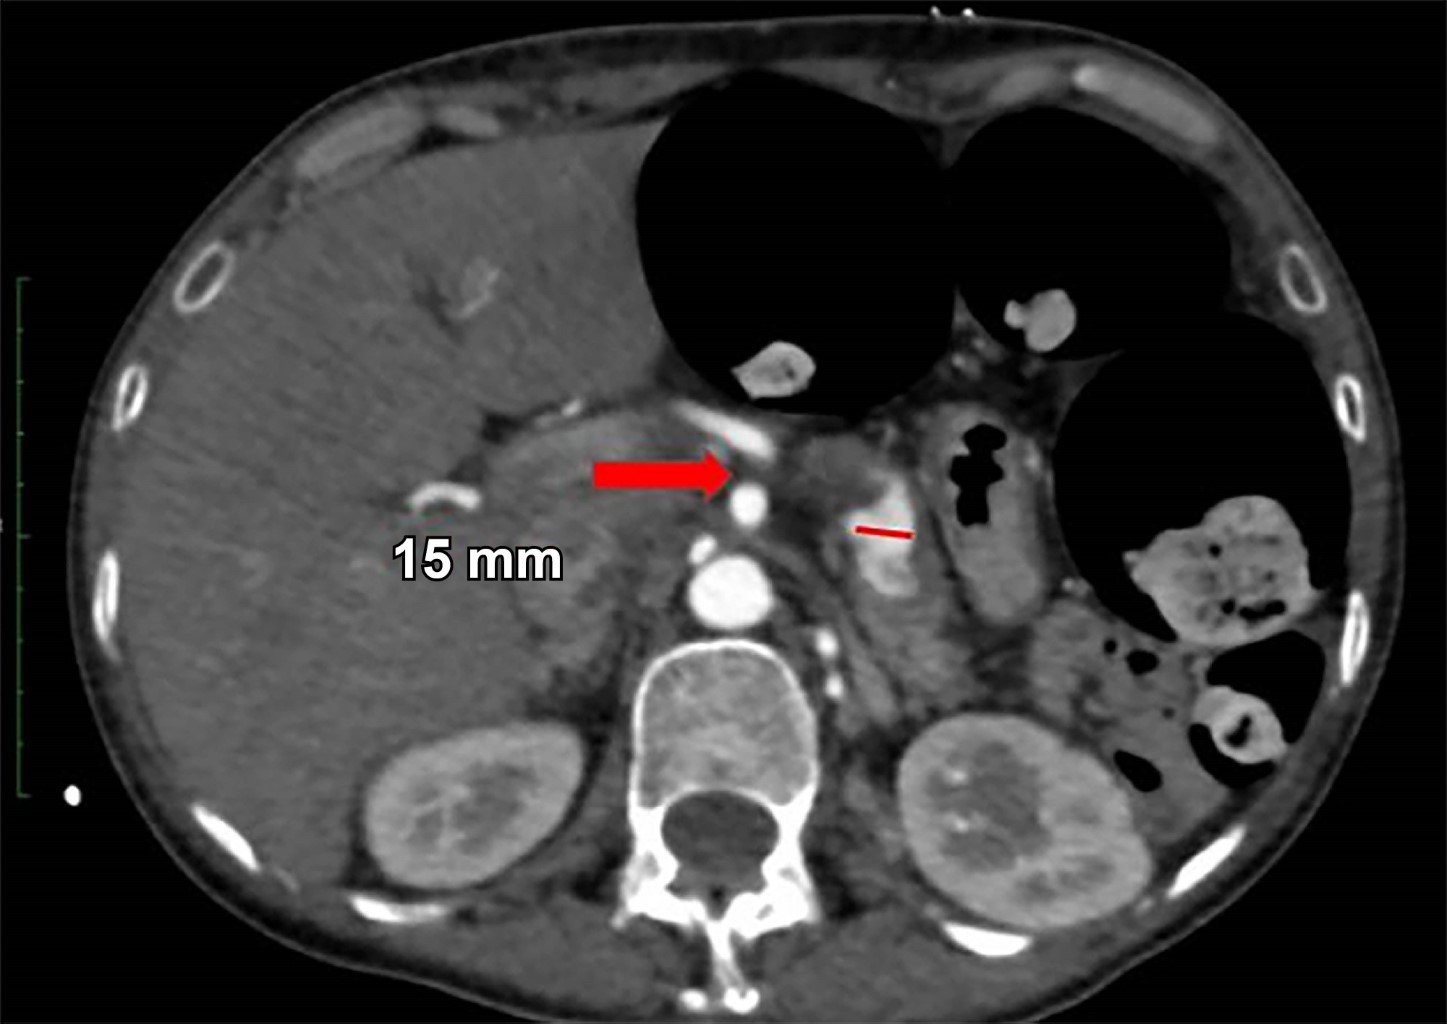

Mujer de 44 años quien 6 meses previos a su ingreso refiere disminución progresiva de la clase funcional debido a un soplo aórtico, por lo que se realizó cambio valvular con la necesidad de ser sometida a circulación extracorpórea y uso de vasopresores. Durante los primeros 10 días postquirúrgicos se diagnostica obstrucción intestinal, por lo que se realiza TC con hallazgo incidental de arteria esplénica (Figura 1) con dilatación aneurismática de hasta 12 mm, en un nuevo estudio de TC a las 24 horas (Figura 2) con ligero aumento del diámetro de aneurisma esplénico hasta 15 mm, pasadas 96 horas solicita nueva TC (Figura 3) y se evidencia mejor definición de la dilatación aneurismática de la arteria esplénica con diámetro actual de 15 mm (previamente de 12 mm). Con los hallazgos tomográficos previamente descritos, se pudo observar la evolución del proceso de dilatación aneurismática con ruptura contenida por el parénquima pancreático, la paciente cursó con un cuadro de obstrucción intestinal con desimpactación endoscópica y dolor abdominal, por lo que seguramente se enmascaró el cuadro clínico.

Figura 2